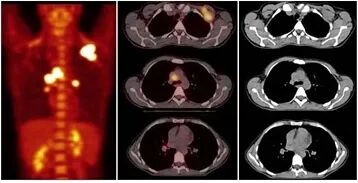

肺癌伴肺不张靶区勾画